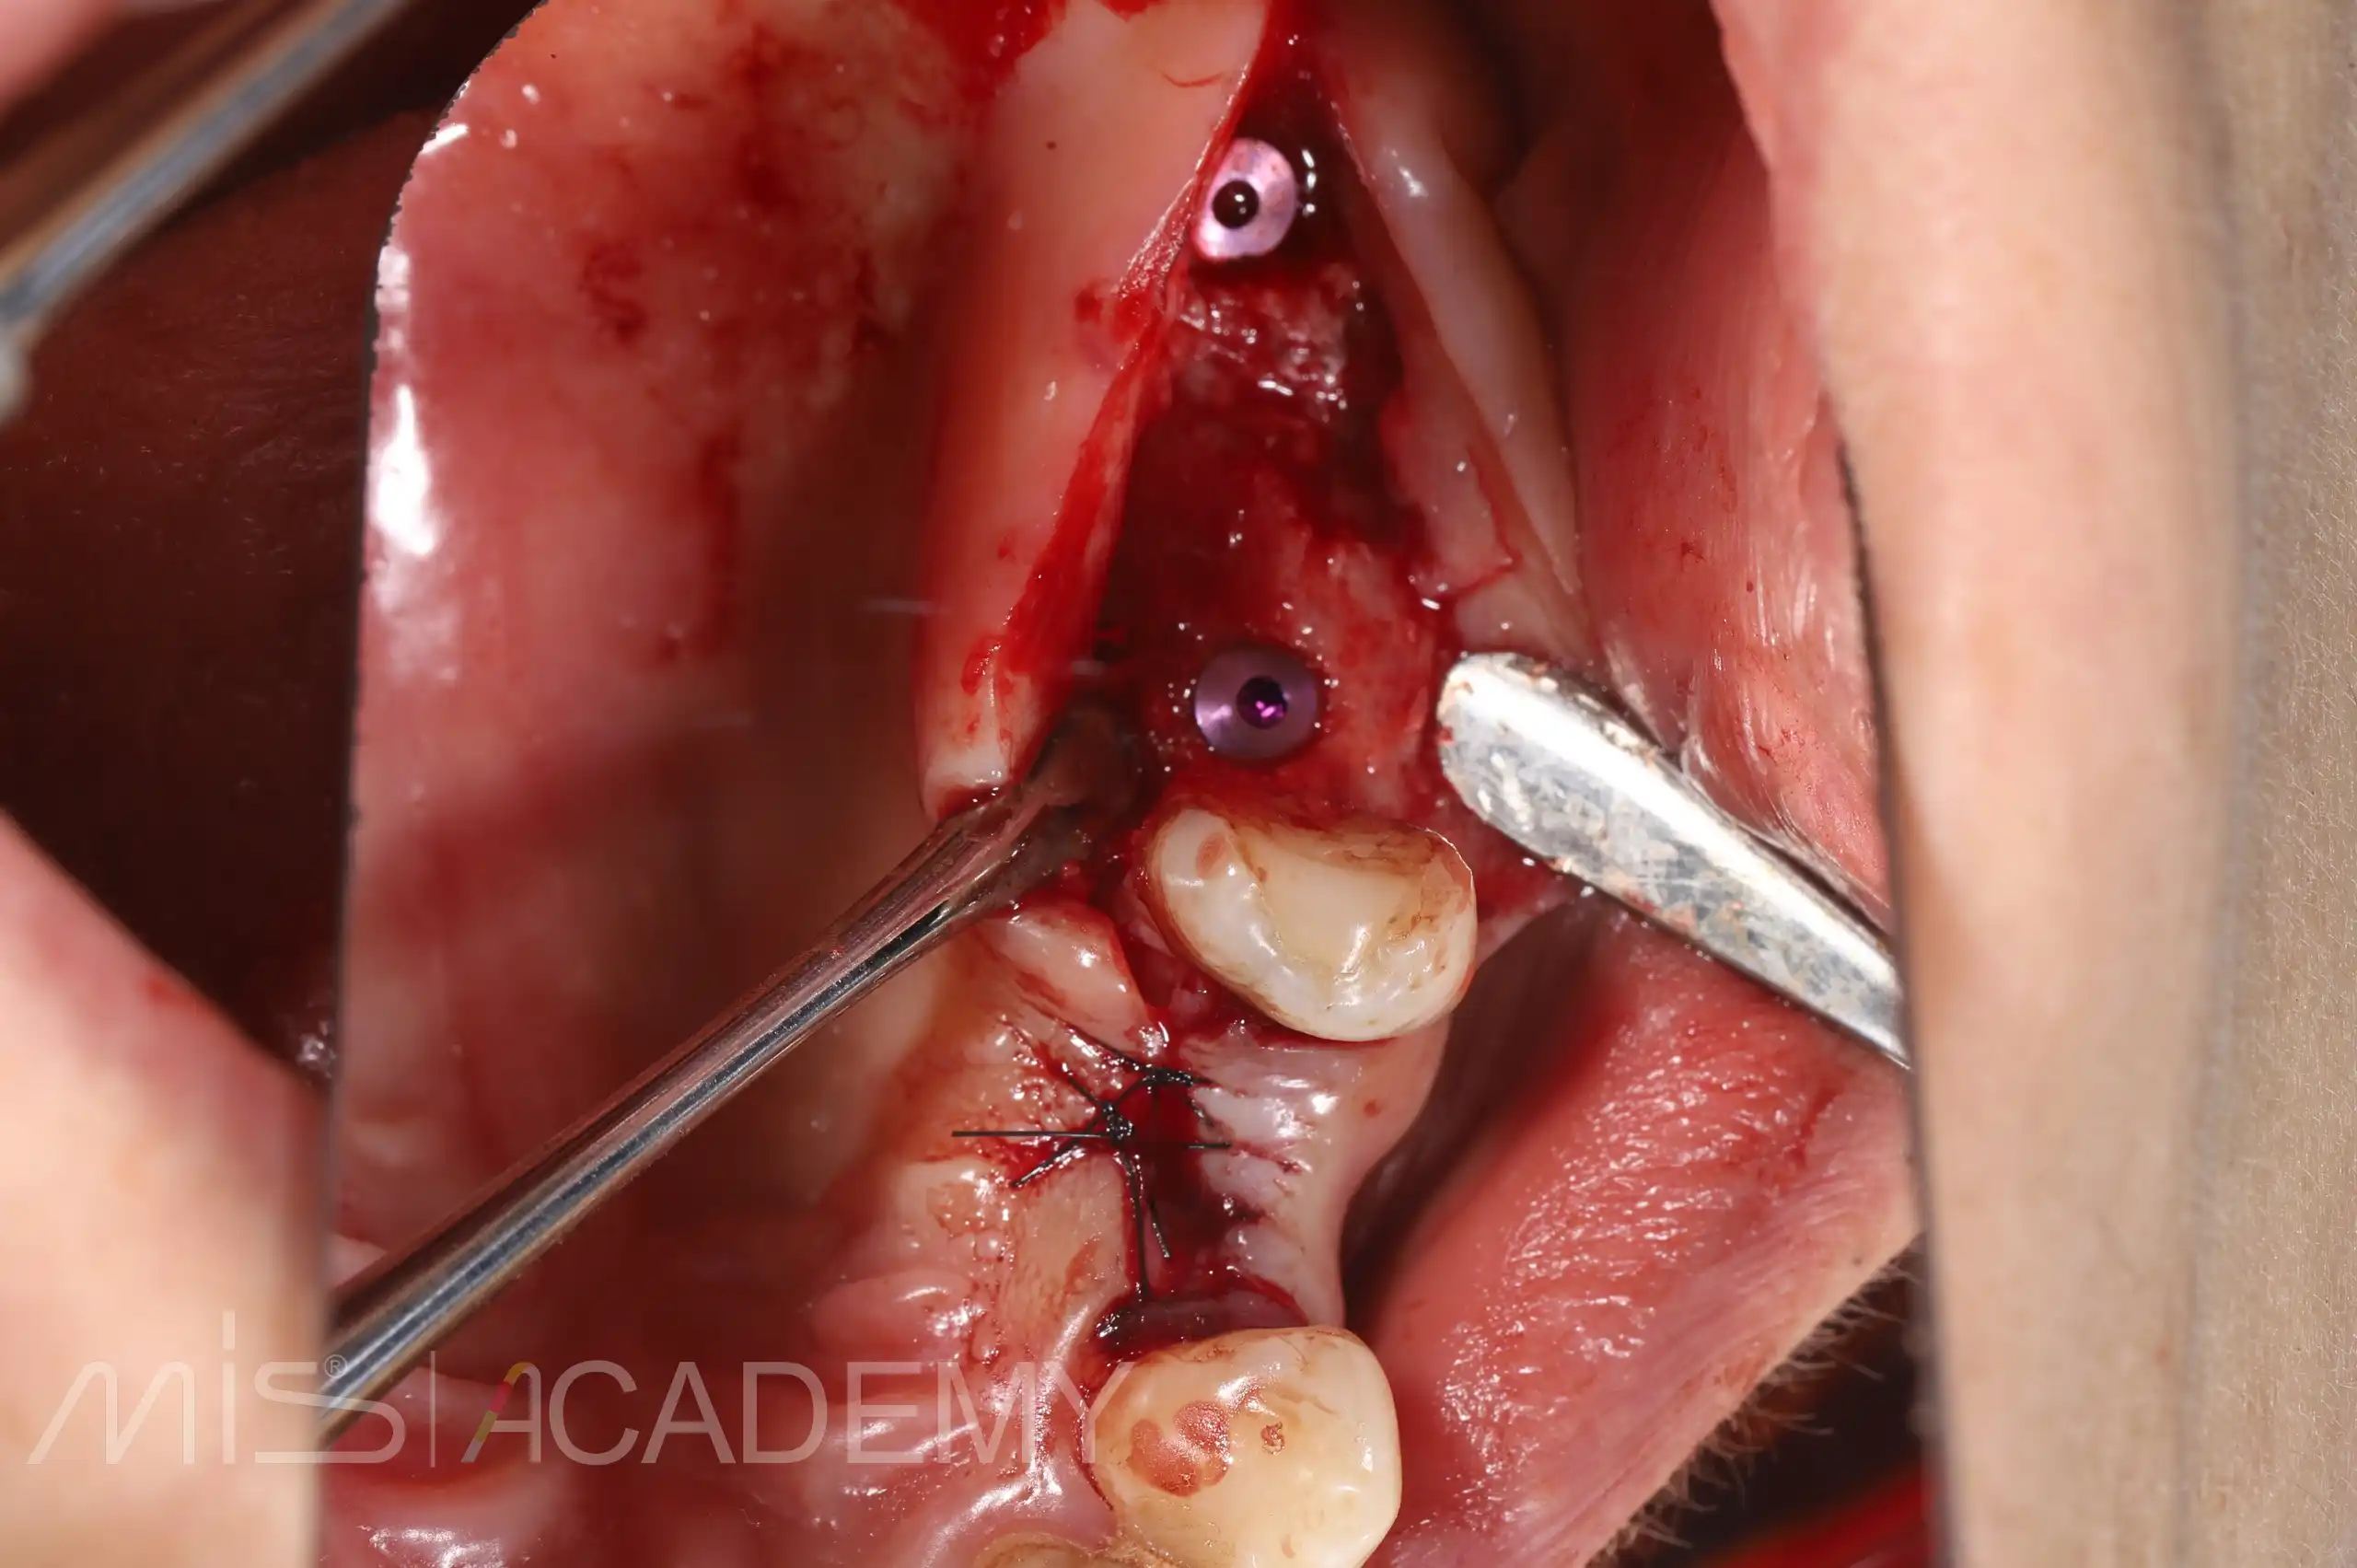

— Через 3 месяца было обнаружено отторжение имплантата в области 2.6, потеря костной ткани в области шейки. Для устранения данного осложнения, во время удаления имплантата 2.6 был фиксирован костный блок, взятый из бугра верхней челюсти справа.

— Одномоментная переустановка имплантата в области 2.6.

— Спустя 3 месяца сделан разрез в области 2.6, удален пин B2S, установлен формирователь десны.